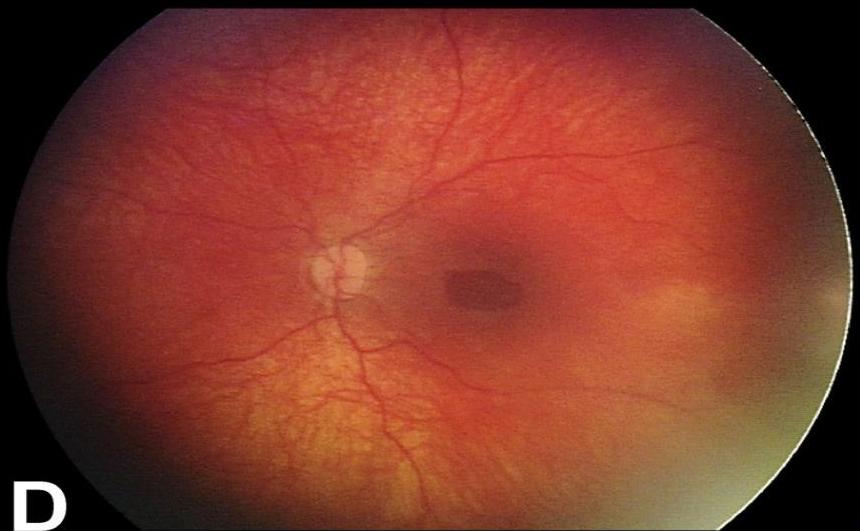

Shaken Baby Syndrome (Abusive Head Trauma)

- Mechanism: Violent shaking causing acceleration-deceleration forces.

- The Triad:

- Subdural Hematoma.

- Retinal Hemorrhages.

- Encephalopathy (diffuse brain injury).